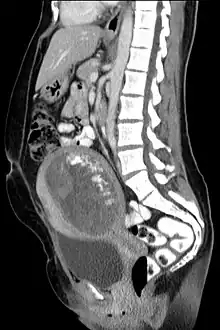

Hydatidiform mole on CT, sagittal view

Hydatidiform mole on CT, axial view

The diagnosis is strongly suggested by ultrasound (sonogram), but definitive diagnosis requires histopathological examination. On ultrasound, the mole resembles a bunch of grapes ("cluster of grapes" or "honeycombed uterus" or "snow-storm").[14] There is increased trophoblast proliferation and enlarging of the chorionic villi, and angiogenesis in the trophoblasts is impaired.[15]